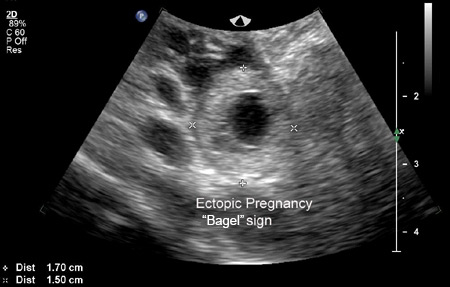

Un embarazo ectópico se visualiza en la ecografía transvaginal (ETV) y el diagnóstico se realiza directamente.[Figure caption and citation for the preceding image starts]: Imagen de ecografía de un embarazo ectópico que muestra el signo de la forma de "rosquilla"De la colección de la Dra. Melissa Fries; usado con permiso [Citation ends].

[Figure caption and citation for the preceding image starts]: Imagen de ecografía de un embarazo ectópico que muestra el signo de la forma de "rosquilla"De la colección de la Dra. Melissa Fries; usado con permiso [Citation ends].

Una masa anexial que se desplaza separada del ovario, a veces denominada "signo del deslizamiento", con un saco gestacional vacío a veces descrito como "anillo tubárico" o "signo del bagel" y una masa anexial compleja, no homogénea, que se desplaza separada del ovario, son altamente sugestivos de un embarazo ectópico, pero no son diagnósticos.[62]